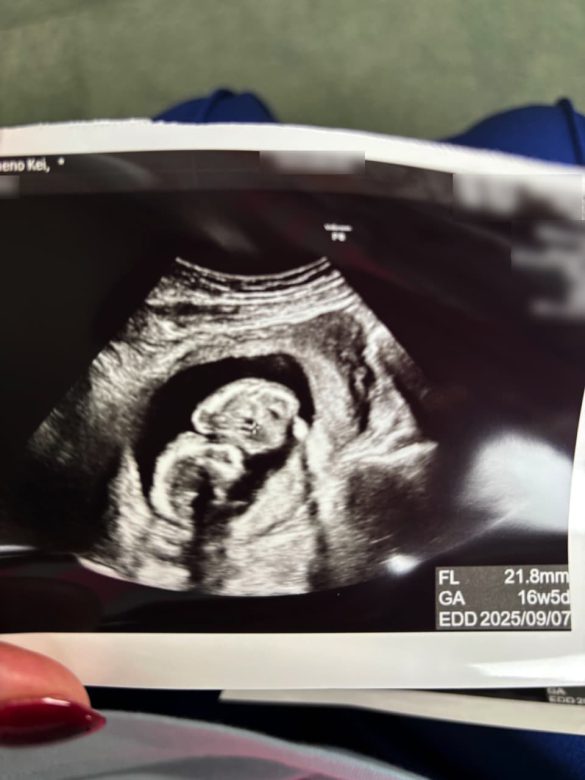

一旦帰宅し、スマホで近所の産婦人科を探して受診した。内診とエコー検査により既に16週に入っていると医師から告げられた。しかも、予定日は私の誕生日である9月7日。我が子と同じ誕生日になる可能性もあることにときめきのようなものを感じた。